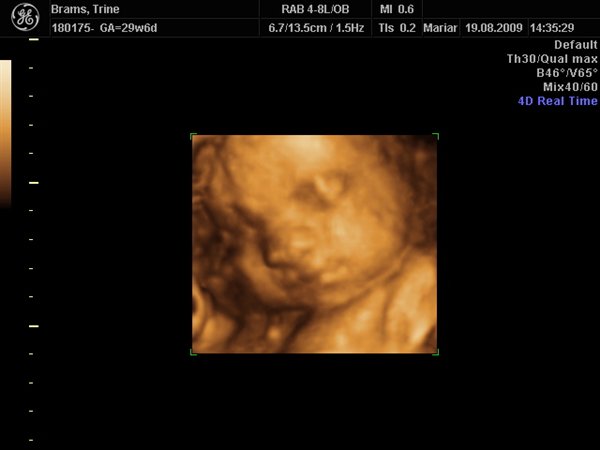

Jeg har lige været til en 3D/4D scanning (27+0), hvilket var en kæmpe oplevelse. Jeg venter en dreng på foreløbig 976 gram

Denne tråd er for alle os som har fået foretaget sådan en scanning. Jeg tænkte det kunne være sjovt at smide nogle fotos op af vores bebzere, da de lå i maven. I profil og forfra.

Skriv gerne hvilken uge scanningen er foretaget, samt evt. hvad køn det er